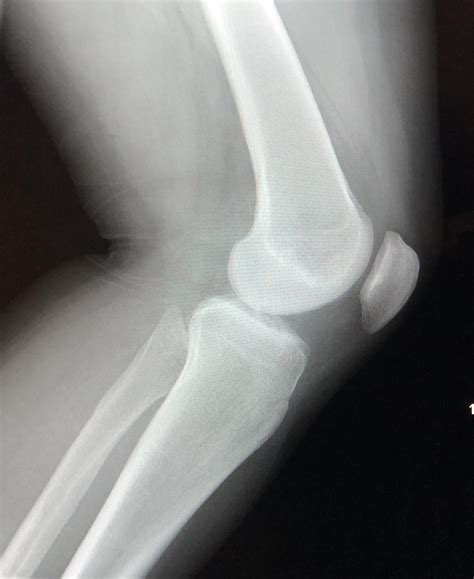

Innovative Scans Will Identify Every Small Bump In My Knee

My Knee Keeps Popping In And Out Of Place | Detroit Chinatown